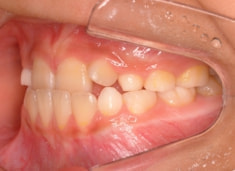

治療前

治療開始時